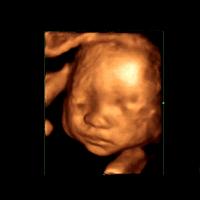

三维彩超和超声影像(四维彩超)的区别主要在于在一个“时间维”,也就是说,三维彩超是图片,是静态的,超声影像(四维彩超)是影像,是动态的,可以让孕妈妈看到胎儿一连串的动作。三维彩超只能是某个时间点上的照片,检查结果比较片面,超声影像(四维彩超)采用四维成像技术,检查结果更为直观,立体,并对目标对象进行连续多维扫描,可以刻录成光盘。

超声影像(四维彩超)是在三维彩超的基础上的一个技术提升,是一个动态的检查过程,仪器要更加先进,影像更加清晰。重要的是,超声影像(四维彩超)能够多方位、多角度地观察宫内胎儿的生长发育情况,为早期筛查胎儿先天性体表畸形和先天性心脏疾病提供准确的科学依据,而且动态记录宫内影像,也比较具有纪念性意义。

1.检查时间:专家建议,超声影像(四维彩超)检查的合适时间单胎为怀孕第22—28周,双胎为20—22周,此时,胎儿的大部分器官已发育,胎儿的大小和羊水量适中,在宫内的活动空间较大,比较容易观察。